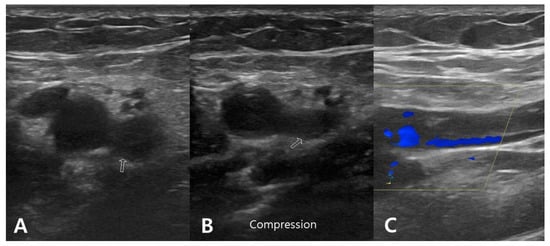

Case Presentation

A 76 year old male presented with painful limitation of motion of the right shoulder. He had a displaced three-part proximal humerus fracture resulting from a slip down. Medical comorbidities included chronic kidney disease, cardiac arrhythmia, and diabetes. The CCI was 7. The patient had no history of hematologic clotting or bleeding abnormalities. The RTSA procedure was performed at 11 days after the initial trauma with an operative time of 115 min. Two days after RTSA, acute brachial vein thrombosis was detected by duplex ultrasonography of the right upper extremity. However, there was no symptoms for DVT. Enoxaparin 20 mg (Xarelto; Bayer Schering Pharma, Berlin, Germany) and warfarin sodium 2 mg (Warfarin; Daehwa Phamaceutical, Seoul, Republic of Korea) were administered for 2 weeks. Warfarin sodium 2 mg was then administered over the next 4 weeks was administered. No complications related to DVT were detected during the serial follow-up evaluation (Figure 1).

Figure 1. Duplex ultrasonographic image from a 76 year old man who underwent reverse total shoulder arthroplasty for proximal humerus fracture. (A,B) B-mode transverse image showing hypoechoic thrombus (arrow) in the brachial vein, which is not compressible by the probe. (C) Longitudinal color Doppler image revealing color filling defect in the brachial vein.